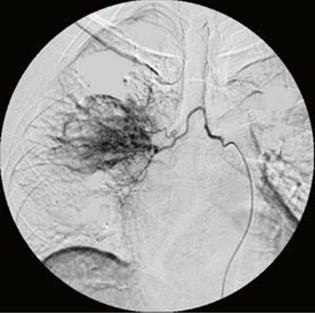

经皮介入栓塞治疗肺癌所致的咯血

另外,当肺癌组织破坏了较大的支气管动脉,造成患者反复、大量咯血,经过内科药物治疗后不能完全止血,同时又无法耐受或不愿接受外科手术治疗时,就可以经过上述管道将具有堵塞作用的药物注射至破裂出血的支气管动脉,堵塞破口以止血。